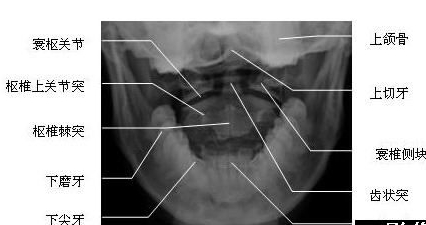

颈椎张口位(图)

颈椎张口位